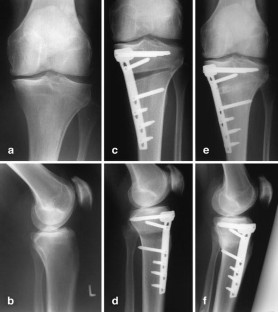

Fig. 8a–f.